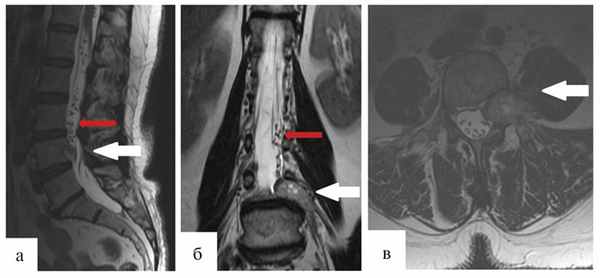

Через 12 мес после операции было выполнено контрольное МРТ-исследование, на котором выявлена та же МР-картина, что и перед операцией (рис. 1).

Рис. 1. Гемангиобластома корешка L4. На серии МРТ, выполненных в сагиттальной, фронтальной и аксиальной проекциях в режиме T2 (а, б, в), определяется экстрадурально расположенное гипоинтенсивное объемное образование на уровне L4—L5 позвонков с гиперинтенсивными очагами и паравертебральным ростом влево по типу «песочных часов» (опухоль указана белыми стрелками). В сагиттальной и фронтальной проекциях (а, б) обращает на себя внимание выраженная сосудистая сеть (указана красными стрелками), которой в Т2-режиме соответствуют множественные зоны гипоинтенсивного сигнала.

После проведенного нами анализа рентгенологических данных можно сделать следующие выводы. Во-первых, все исследования должны проводиться с контрастным усилением. Во-вторых, обнаружение патологически расширенных извитых сосудов в пределах позвоночного канала вокруг новообразования является патогномоничным признаком гемангиобластомы. Лучше всего сосуды визуализируются в Т2-режиме. В-третьих, солидный компонент опухоли имеет гипо- или изоинтенсивный МР-сигнал в Т1-режиме, а кистозные полости имеют сходный с ликвором сигнал в Т1- и Т2-режимах, или более яркий сигнал в режиме Т2. Выявление хотя бы одного из этих перечисленных МРТ-признаков дает основание предполагать опухоль сосудистого ряда и может быть рекомендовано выполнение селективной ангиографии [4, 5].